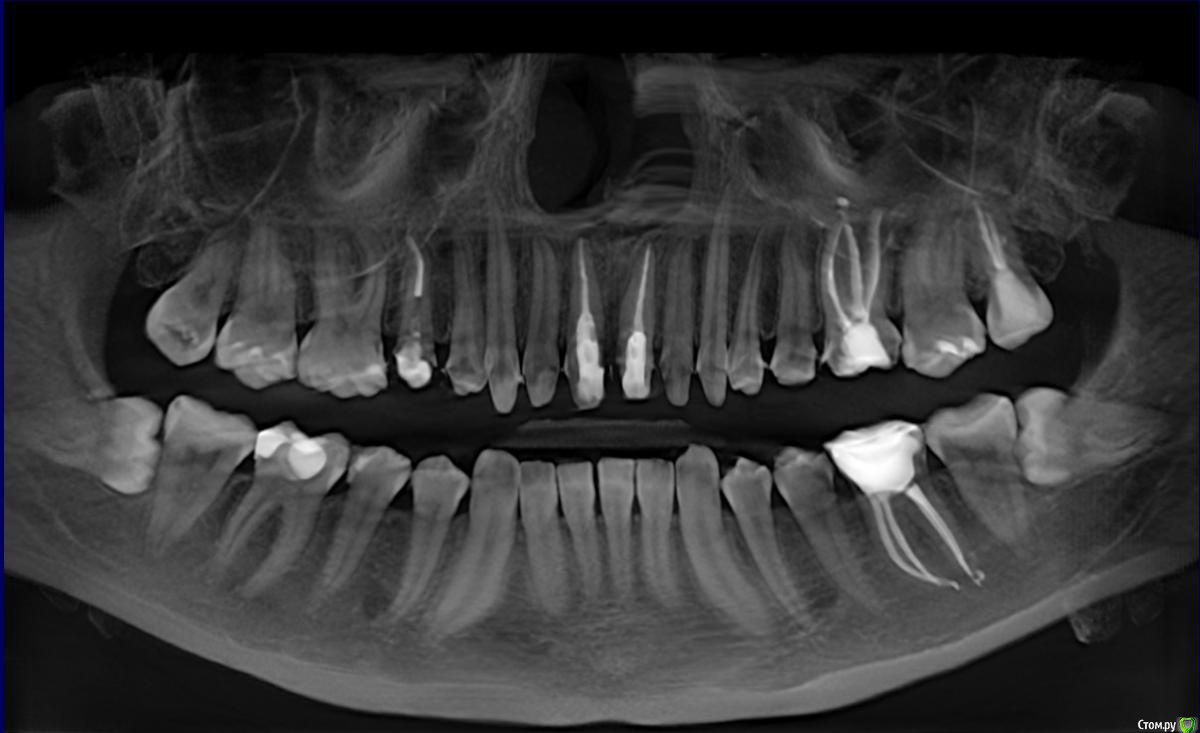

alix Опубликовано 14 сентября, 2017 Поделиться Опубликовано 14 сентября, 2017 Здравствуйте.Уже писала здесь пост, но он был слишком эмоциональный и не информативный, без снимка. Поэтому пишу снова и постараюсь вкратце пояснить проблему.С середины июля ведется установка 11 коронок на верхней челюсти. 7 зубов живые. Ставятся с косметической целью скрыть дефекты эмали (флюороз) Временные коронки неоднократно менялись (в общем целом около шести раз). На данный момент стоят коронки, которые не устраивают по прикусу. Присутствует боль на накусывание всех живых зубов под коронками. Изначально болела только правая двойка, затем, после смены коронок присоединились правые тройка и четверка. Когда в очередной раз установили последние времянки - заболели и все остальные живые зубы тоже. Повторюсь, что существенная боль только на накусывание, сами по себе зубы изредка слегка ощущают легкую покалывающую боль. Есть терпимая чувствительность на холодное, на воздух.Доктора в клинике уверяют, что если поставить постоянную конструкцию, то боль скорее всего уйдет, так как цемент загерметизирует все канальцы в дентине, будет плотное прилегание к десне или типа того. Так же ссылаются на неправильный прикус и неправильно смыкание, что боли могут быть из-за этого, они его исправят, все пройдет. Депульпировать зубы не хотят, так как не видят никаких показаний. Если зуб заболит под коронкой, то говорят, что просверлят дырочку и депульпируют зуб.Я решила сходить в другую клинику и поинтересоваться мнением другого специалиста. Он уверяет, что ставить постоянные коронки на зубы с болью ни в коем случае нельзя, так как сейчас конструкция мягкая, а потом будет жесткая и зубы могут заболеть еще больше, поэтому скорее всего нужна депульпация. Так же отмечает, что зубы обточены до дентина, а значит туда могла инфекция, тем более учитывая, что времянки несколько раз меняли и они не защищают живой зуб на 100%. Не знаю, кому верить. Подскажите, пожалуйста, что делать в моей ситуации. Кто из врачей прав? Ссылка на комментарий

alix Опубликовано 16 октября, 2017 Автор Поделиться Опубликовано 16 октября, 2017 Качественных фотографий ситуации "до" нет, но есть такое: Ссылка на комментарий